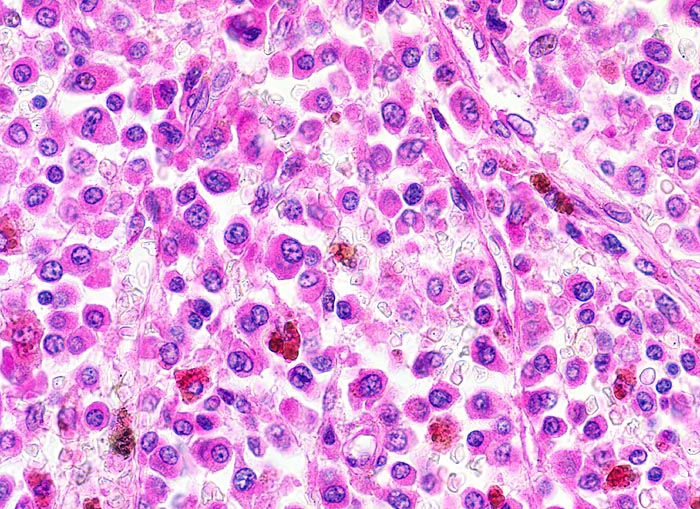

Plasmazellmyelom

Knochenmark, Wirbelkörper

Tumor ausschliesslich aus atypischen Plasmazellen zusammengesetzt: exzentrisch gelagerte Kerne, ausladendes Zytoplasma. Grobes, randständiges Heterochromatin, im typischen Fall mit Radspeichenstruktur.

Histologie

400